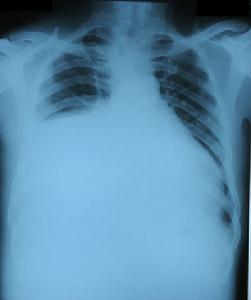

多器官功能不全綜合徵1、肺臟 低氧血症,需機械通氣支持至少3-5d。

各系統器官的功能障礙,有的在臨床方面表現比較明顯,有的要待病變進展到相當程度才有明顯的臨床表現。心血管、肺、腦和腎的功能障褥大多表現明顯;而肝、胃腸和血液凝固系統等的功能障礙,至較重時才有明顯的臨床表現。利用化驗,心電診斷、影像和介人性監測,方法,可以較早且較為準確地發現器官功能障礙。例如:血氣分析可以顯示肺換氣功能;尿比重和血肌酐等的測定可以顯示腎功能;心電圖和中心靜脈壓、平均動脈壓監測、經Swan-Ganz導管的監測可以顯示心血管功能;等等。所以,MODS的診斷需要臨床表現和醫技檢查結果的綜合分析。